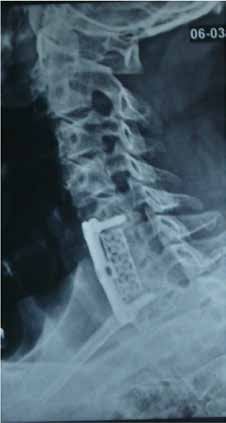

Cervical Multilevel

Long Mash cage